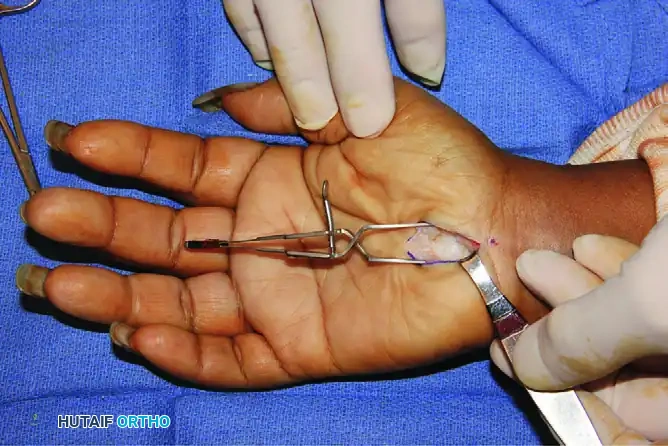

Step 2: Superficial Dissection and Exposure

- Incise the skin and subcutaneous tissue sharply.

- Identify the palmar fascia. Using subcutaneous blunt dissection, retract the parallel palmar fascia fibers and the hypothenar fat pad to expose the underlying transverse carpal ligament (TCL).

- Self-retaining retractors (e.g., a Weitlaner or specialized hand retractors) are placed to maintain a clear visual field.

Exposure of the transverse carpal ligament (TCL) following the retraction of parallel palmar fascia fibers and hypothenar fat.